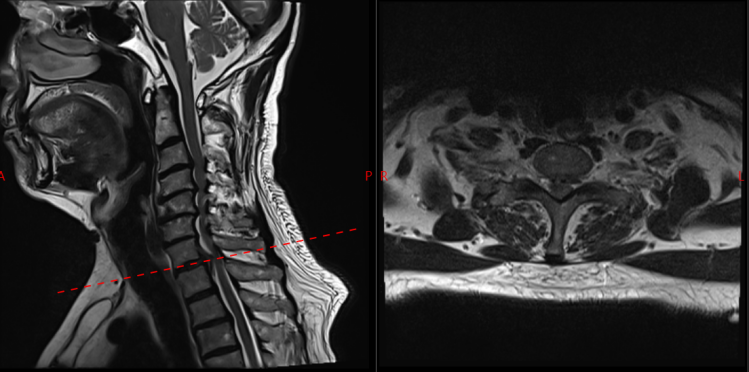

面对这一特殊情况,吴静晔主任没有急于下结论,而是为患者进行了细致全面的检查,最终精准诊断为脊髓型颈椎病。而进一步检查显示,患者存在C3-T1多节段狭窄,病情复杂且手术节段较多,这无疑给治疗带来了巨大挑战。

通过与骨科手术机器人配合,整个手术过程顺利完成,螺钉置入位置精准无误,患者术中出血量大幅减少,手术时间也得到有效优化,手术效率和安全性实现双重提升。

术后复查结果也令人振奋,患者螺钉位置良好,椎管减压彻底,原本麻木、无力的双下肢症状明显改善,行走能力逐步恢复。看着老先生摆脱病痛困扰,脸上重新露出笑容,医护人员也倍感欣慰。